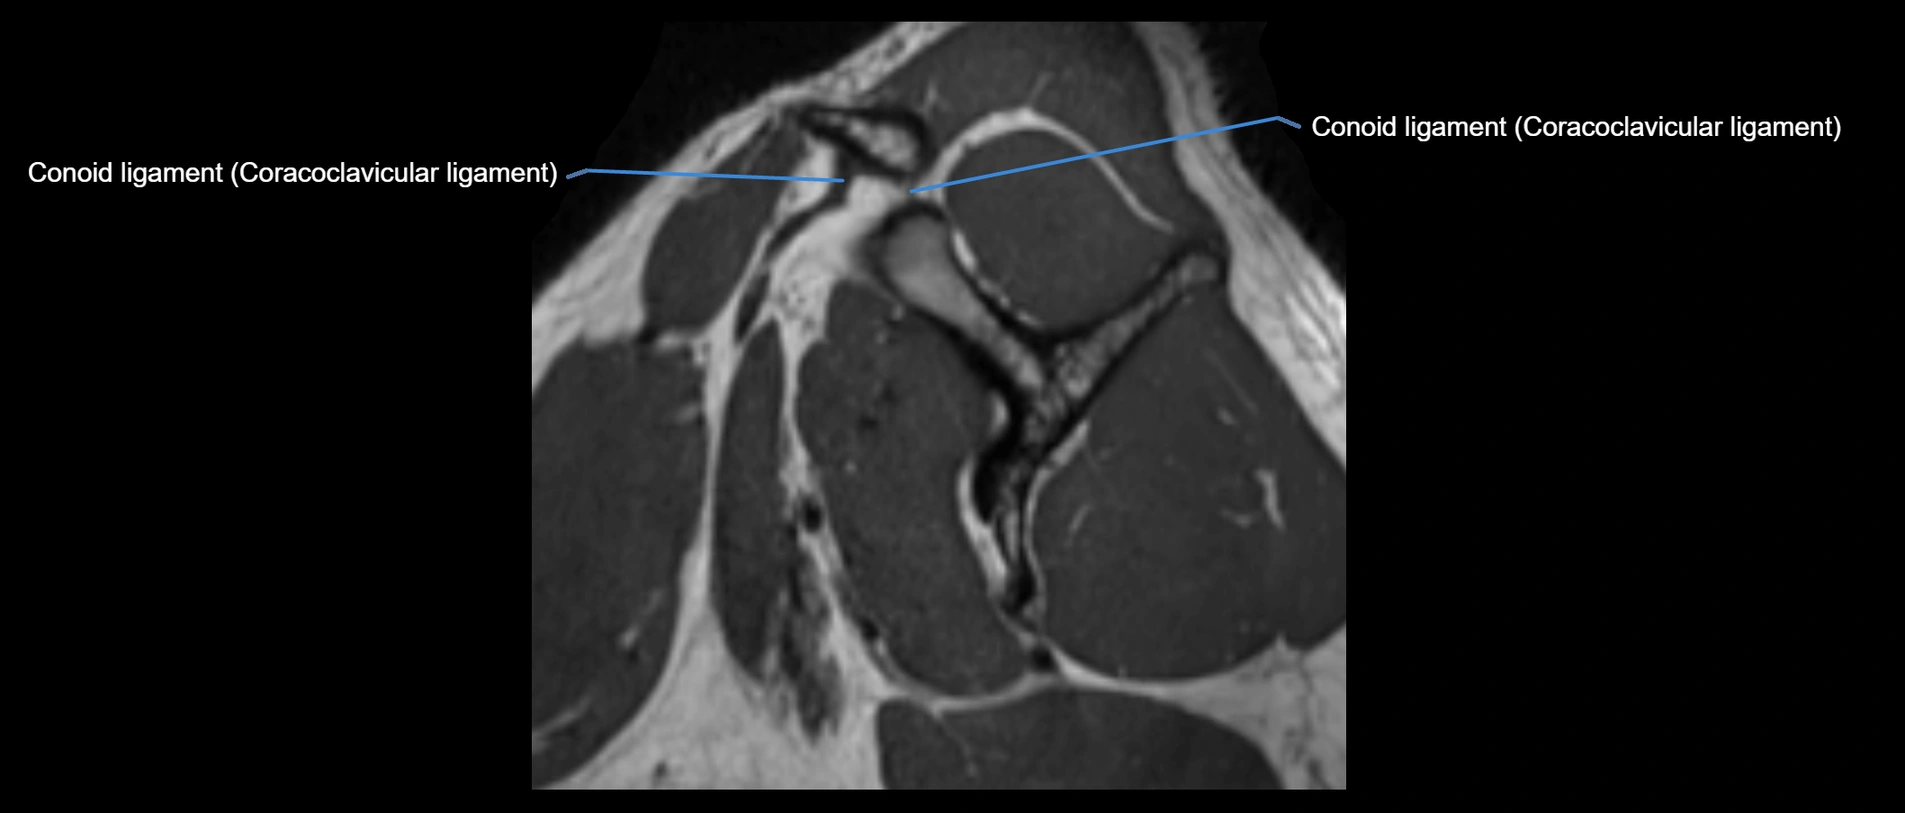

MRI images

image

MRI Appearance

• T1-weighted images:

• Normal ligament: Low signal (dark linear band) spanning acromion to clavicle.

• Surrounding fat planes: Bright, delineating the ligament clearly.

• Marrow of clavicle and acromion: Bright due to fatty content.

• Tears: Discontinuity or irregular thickening with intermediate-to-bright signal.

• Chronic injury: Thinning, fraying, or irregular low-signal fibers with adjacent scarring.

• T2-weighted images:

• Normal ligament: Low signal, homogeneous.

• Partial tear or sprain: Focal hyperintensity or thickening.

• Complete tear: Discontinuity with fluid-bright gap between clavicle and acromion.

• Associated edema: Bright signal in distal clavicle or acromion marrow.